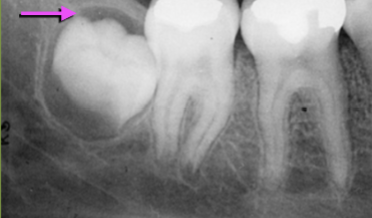

Describe this Radicular Cyst

Epicenter at apex (usually evidence of dental disease or trauma)

Well-defined, corticated

Lucent

Circular

Resorption, Displacement, Expansion (effect on adjacent structures)